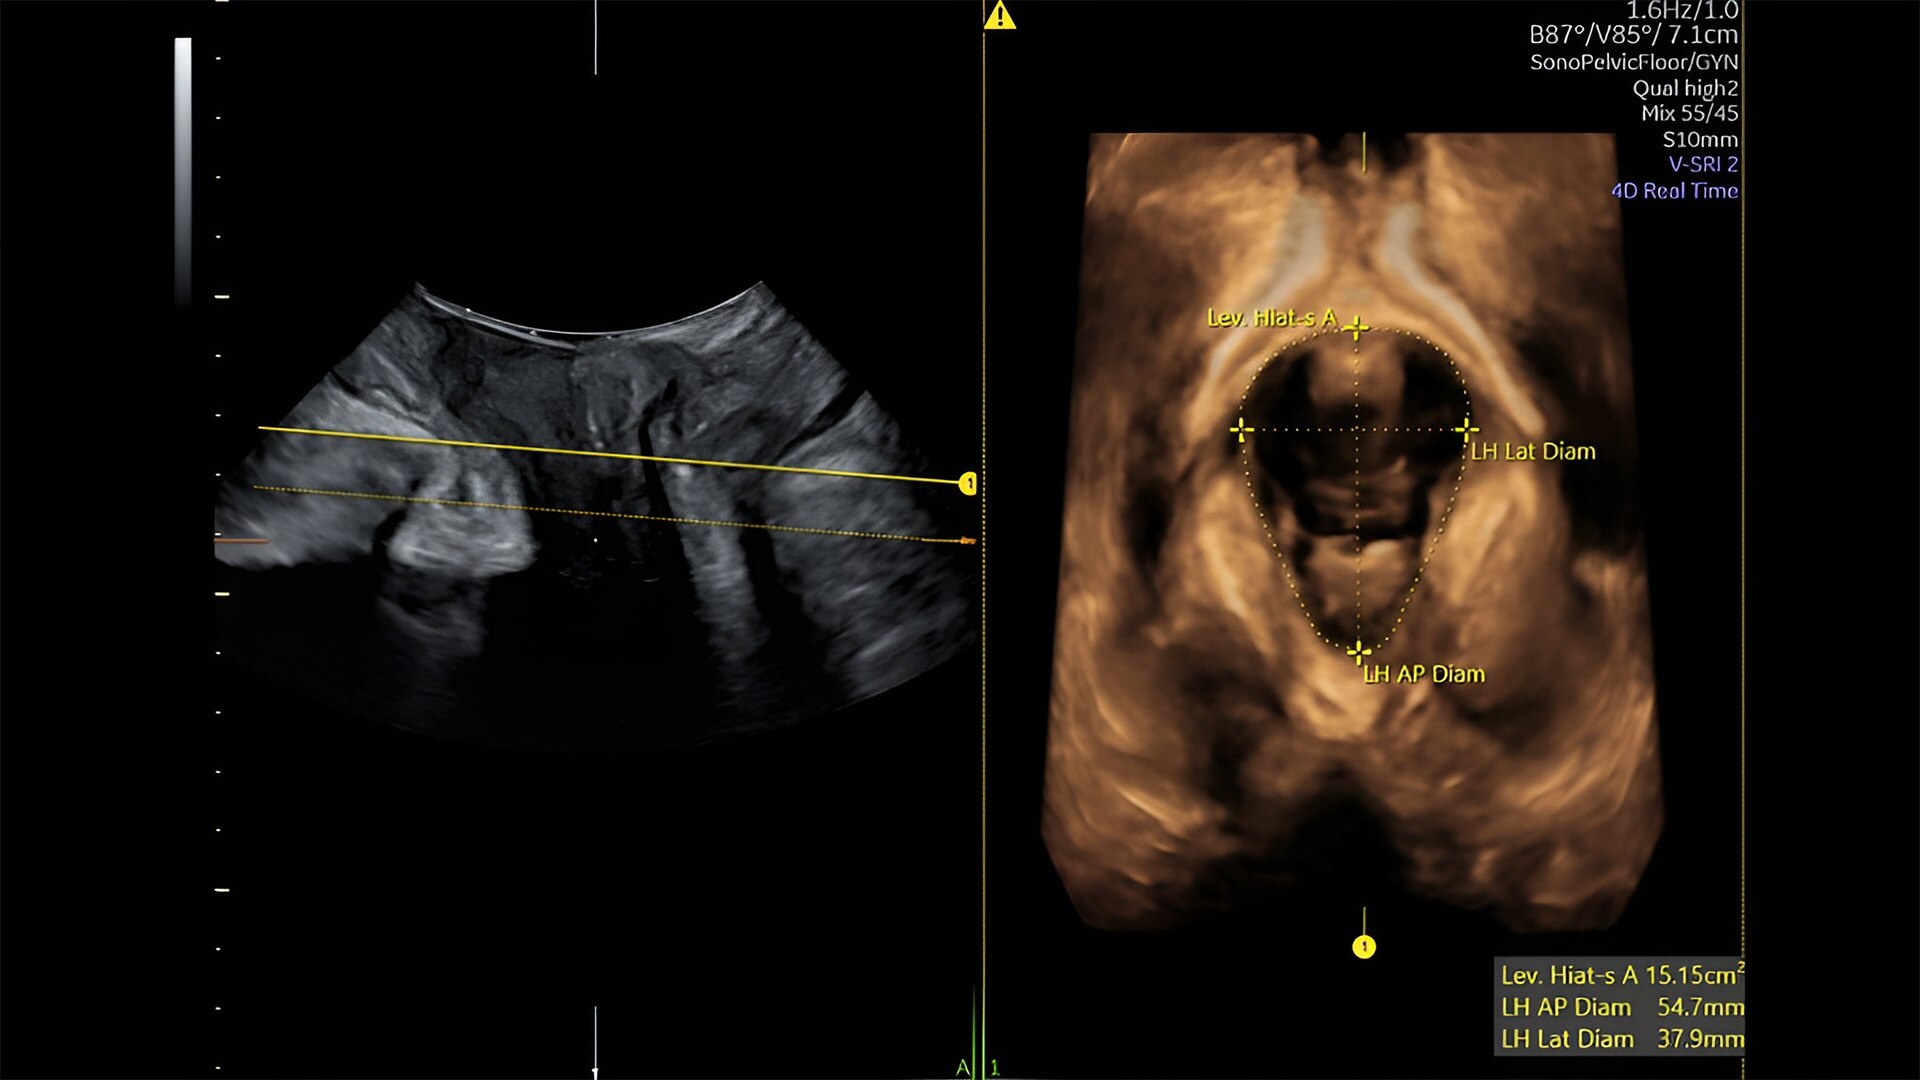

Pelvic health

Offer patient answers faster with Ai-based automation tools